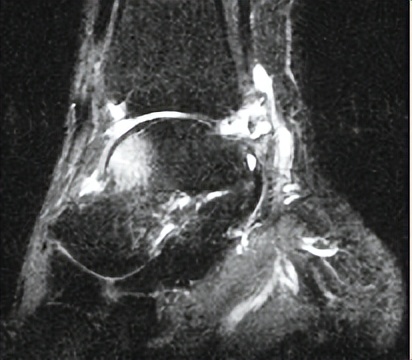

MRI检查:可以清楚显示踝关节周围软组织、韧带、软骨、骨结构的改变,对踝关节损伤严重程度和滑膜病变做出良好判断,为踝关节撞击征的诊断提供重要参考依据。

MRI检查可见关节前方距骨水肿,后方出现软组织撞击、局部积液肿胀